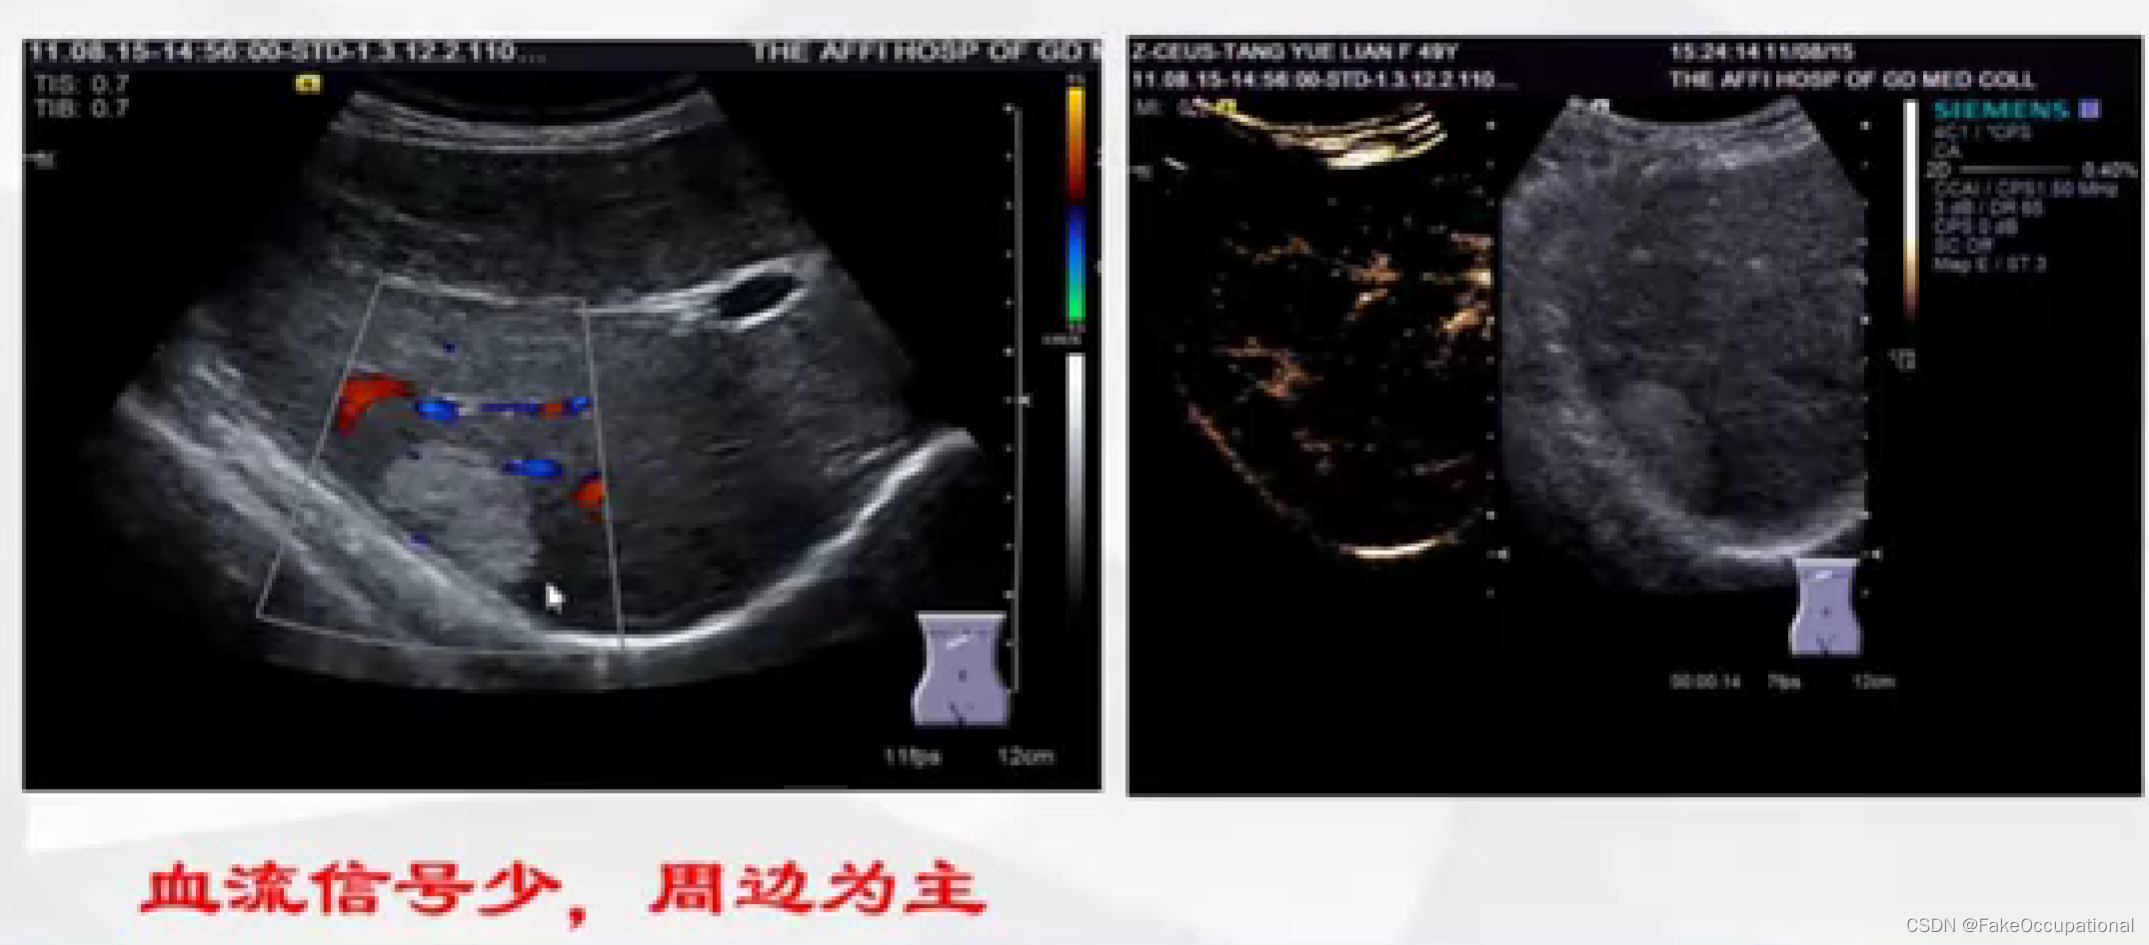

- 彩色编码实时显示血流方向、速度及血流性质:彩色多普勒血流成像(CDFI),彩色多普勒能量图(CDE)